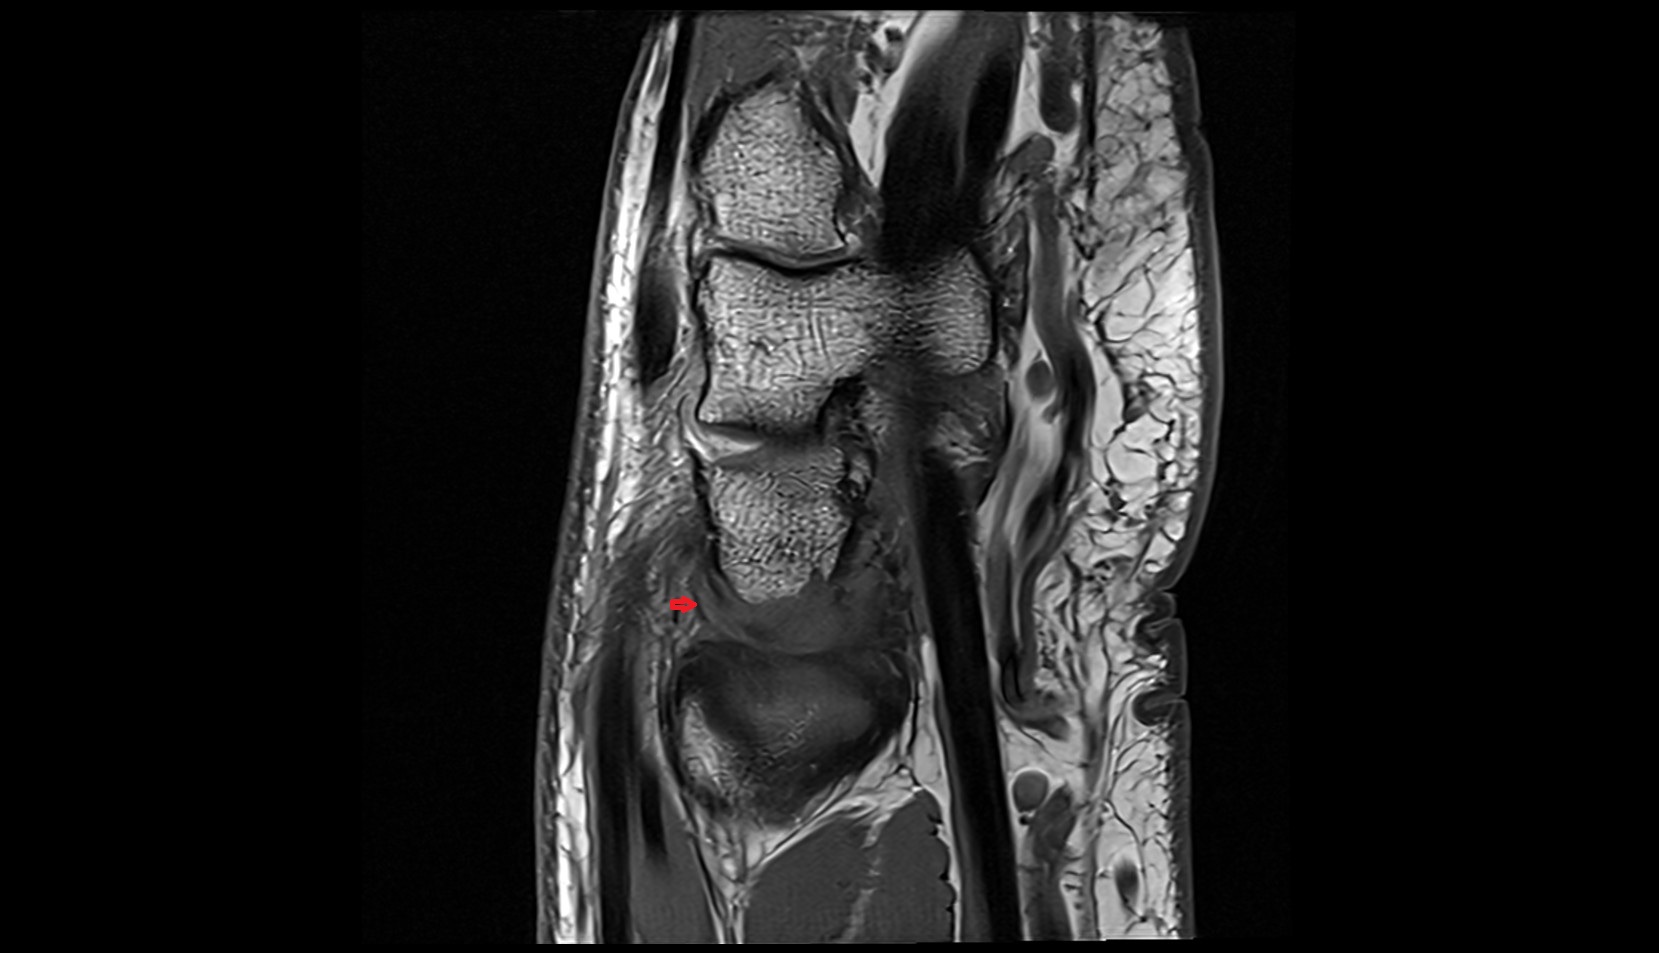

- Anterior cruciate ligament

- Posterior cruciate ligament

- Infrapatellar fat pad

- Suprapatellar fat pad

- Prefemoral fat pad